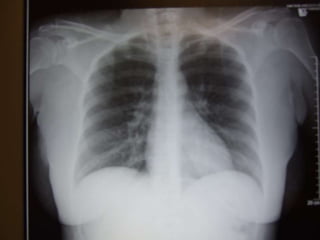

 Diffuse infiltrates

 CXR – diffuse alveolar infiltrates

 Severe endof the spectrum of acute lung injury  Acute and persistent lung inflammation with increased vascular permeability  Diffuse infiltrates  Hypoxemia – paO2/FiO2 <200  (i.e. pO2 70 / FiO2 0.5 = 140)  No clinical evidence of elevated left atrial pressure (PCWP <18 if measured)

 Early  Incitingevent, pulmonary dysfunction (worsening tachypnea, dyspnea, hypoxemia)  Nonspecific labs  CXR – diffuse alveolar infiltrates  Subsequent  Improvement in oxygenation  Continued ventilator dependence  Complications  Large dead space, high minute ventilation requirement  Organization and fibrosis in proliferative phase